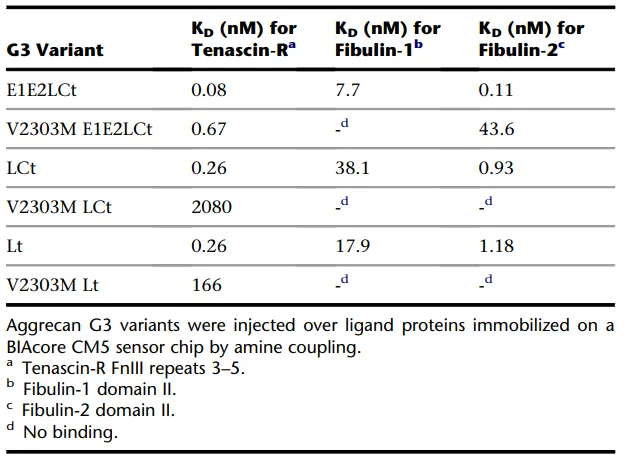

随后,研究人员又研究了其他胞外基质蛋白与Aggrecan蛋白及其突变体的互作情况。他们将胞外基质蛋白tenascin-R、fibulin-1和fibulin-2固定在CM5传感芯片的不同通道,将三种野生型以及三种V2303M G3结构域突变体Lt/LCt/E1E2LCt Variant流经芯片表面,检测互相的亲和力/动力学。结果如表1所示,所有V2303M G3突变体与细胞外基质蛋白tenascin-R、fibulin-1和fibulin-2的结合均受到影响,均显示亲和力减弱或完全丧失。这清楚地表明家族性剥脱性骨软骨炎相关的V2303M突变影响正常的Aggrecan G3结构域功能。

表1 不同G3结构域野生型、突变体和不同胞外基质的结合情况